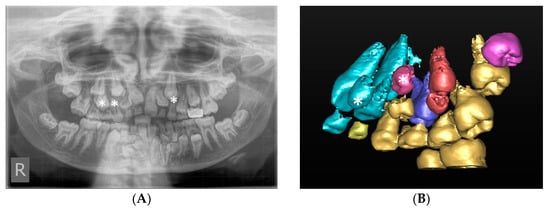

The presence of supernumerary teeth can pose a challenge to the clinician’s ability to distinguish the supernumerary from the true tooth, as illustrated in Figure 4. This case was referred for CBCT to differentiate the true lateral incisor tooth and the supplemental tooth. The supplemental lateral incisor was identified as the palatally positioned tooth, following a CBCT assessment of the more rudimentary tooth morphology. Precise morphological measurements and accurate localisation of teeth from CBCT images allow the clinician to make an informed decision on which tooth to extract and the optimal surgical approach to reduce the risk of damage to the true tooth.

Figure 4.

(A) The upper standard occlusal shows a supplemental tooth in the maxillary left lateral incisor area. It is difficult to discern from the conventional views which of the two teeth, marked with a white and a black asterisk would be morphologically optimal to serve as the lateral incisor. (B) CBCT axial view of the left maxilla. An analysis of the dimensions of the teeth revealed that the tooth marked with the white asterisk was smaller compared to the adjacent unerupted tooth and the contralateral lateral incisor, and as such, more likely to represent the supplemental lateral incisor.